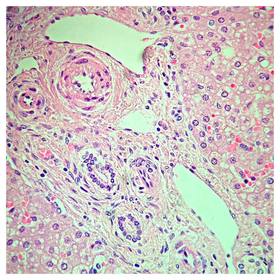

Láminas de Histología

Laboratorio de histología, Bibliografía Ross Pawlina 5ta Edición.